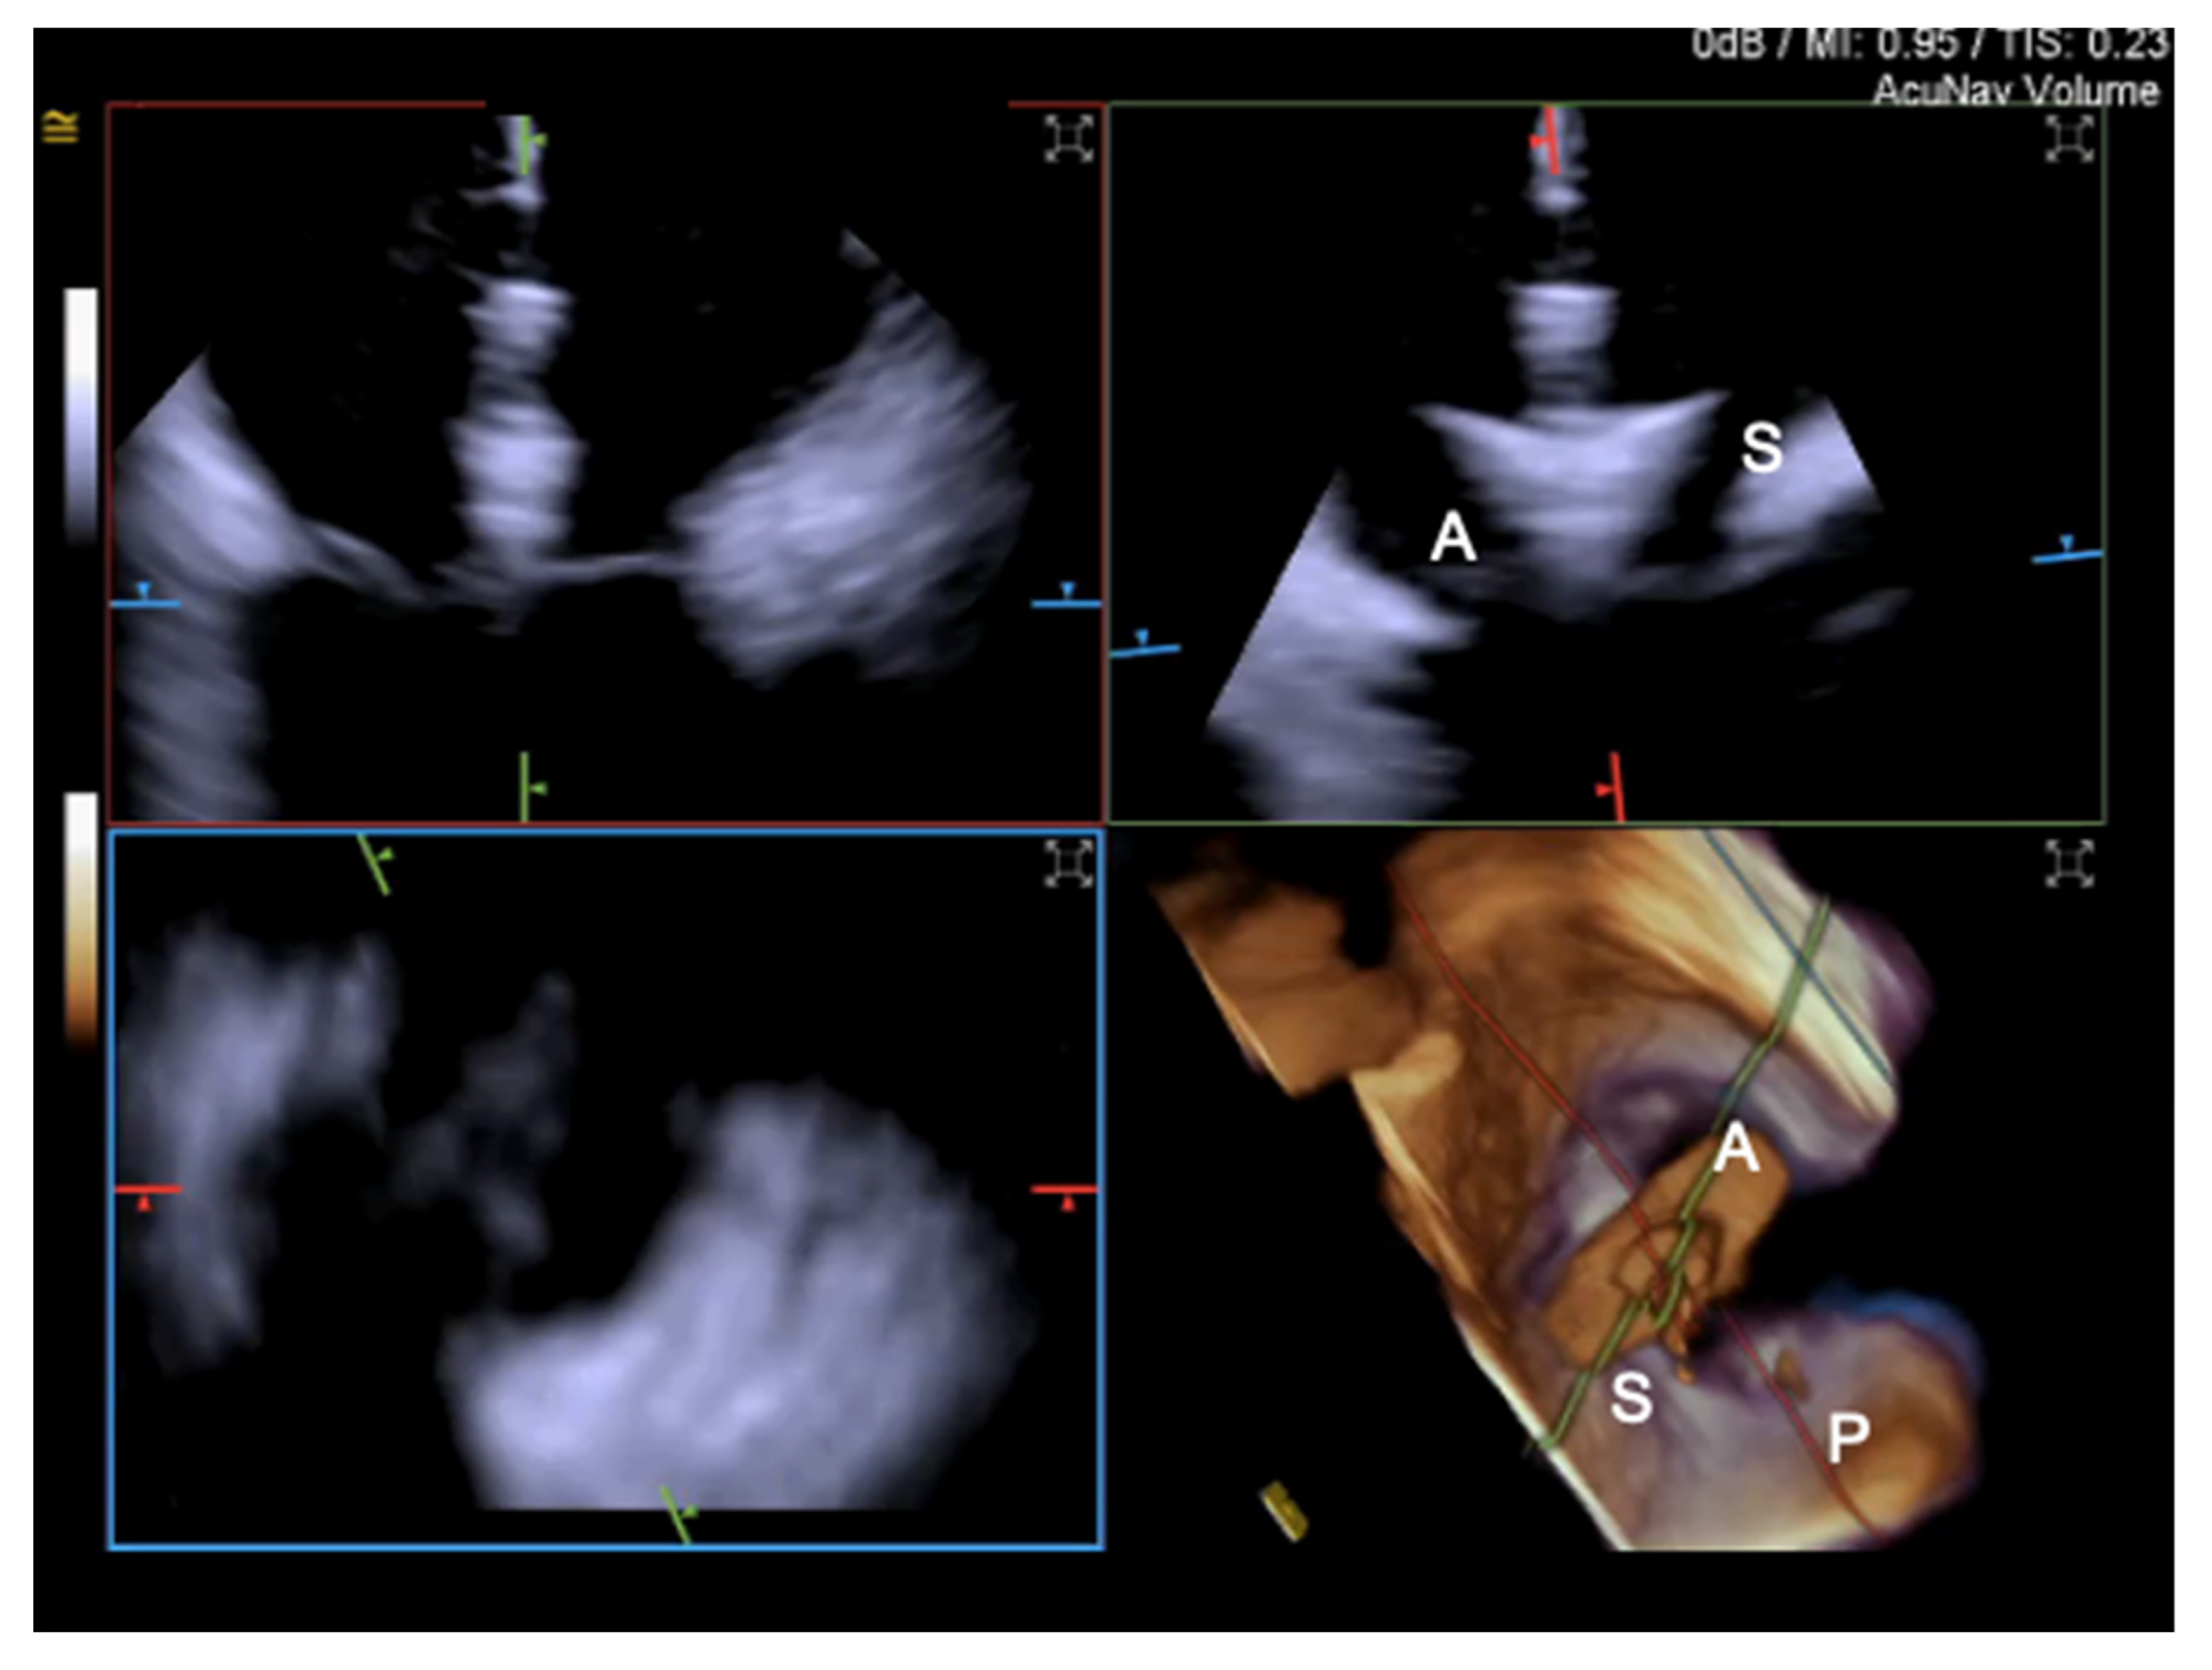

- Tang, G.H.; Yakubov, S.J.; Soto, C.E.S. 4-Dimensional Intracardiac Echocardiography in Transcatheter Tricuspid Valve Repair with the MitraClip System. JACC Cardiovasc. Imaging 2020, 13, 1591–1600. [Google Scholar] [CrossRef]

- Silvestry, F.E.; Kadakia, M.B.; Willhide, J.; Herrmann, H.C. Initial experience with a novel real-time three-dimensional intracardiac ultrasound system to guide percutaneous cardiac structural interventions: A phase 1 feasibility study of volume intracardiac echocardiography in the assessment of patients with structural heart disease undergoing percutaneous transcatheter therapy. J. Am. Soc. Echocardiogr. 2014, 27, 978–983. [Google Scholar] [CrossRef]